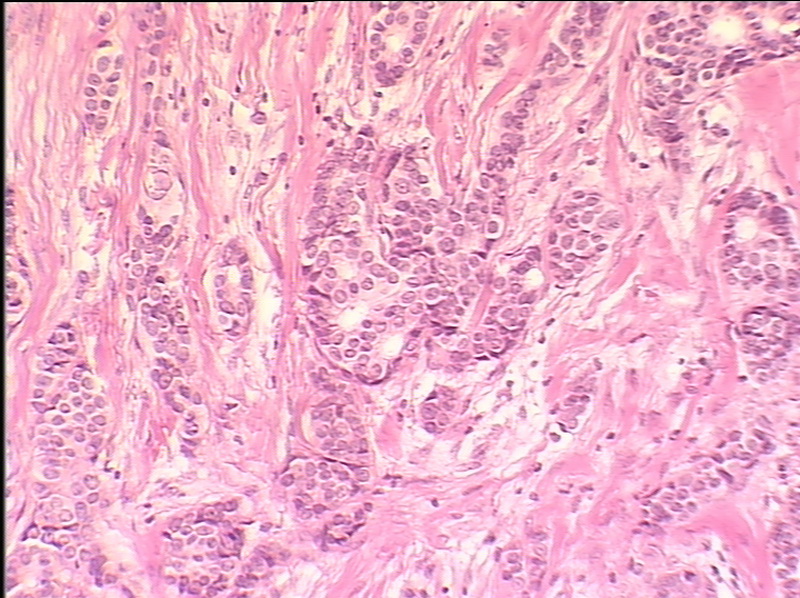

Фотографии опухоли медуллярной аденокарциномы